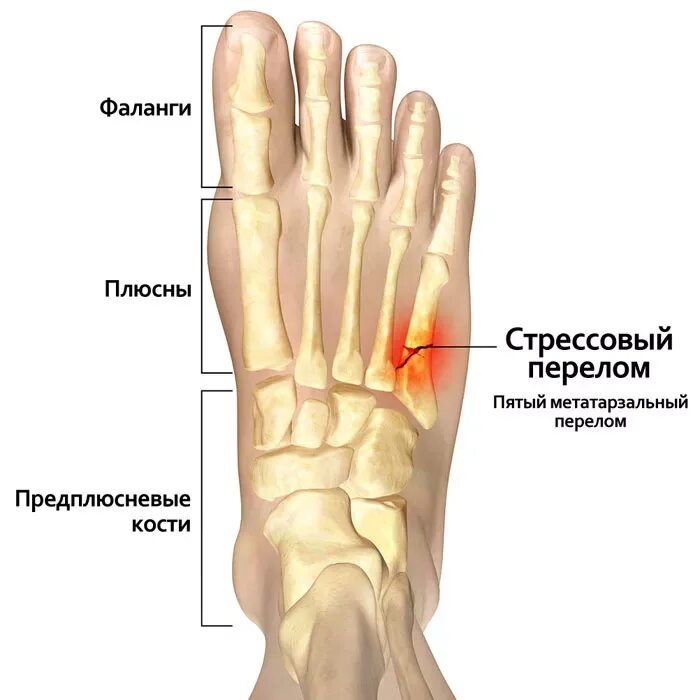

Как определить перелом стопы